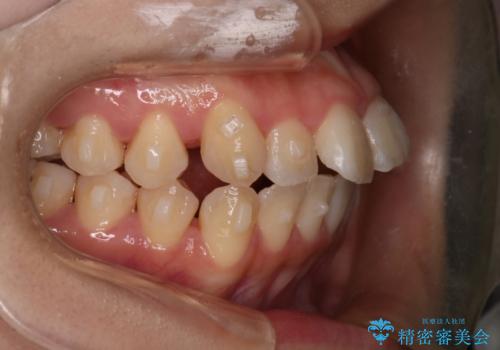

【インビザライン】マウスピースで開咬改善

- 開咬を主訴に来院されました。

IPR(歯と歯の間を削る処置)と顎間ゴムを行いながら、インビザラインで開咬を治療する計画を立てました。

治療をしながら、MFT(口腔筋機能療法)も行っていくことにしました。

歯の移動量が多いケースでしたが、患者様にマウスピースの使用とゴム掛けを頑張っていただいたので

リファイメント1回のみで治療を終わることができました。